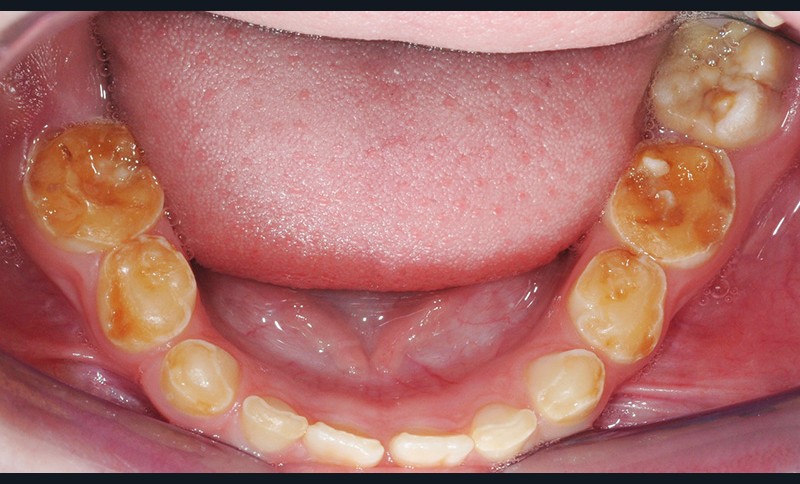

Quel est le principal diagnostic différentiel ?

(fig. 2 et 3)

Il s’agit de l’amélogénèse imparfaite héréditaire, qui :

• touche toutes les dents de l’arcade ;

• entraîne une coloration jaune orangée de l’émail sur toute la surface coronaire ;

• est liée à une étiologie génétique.